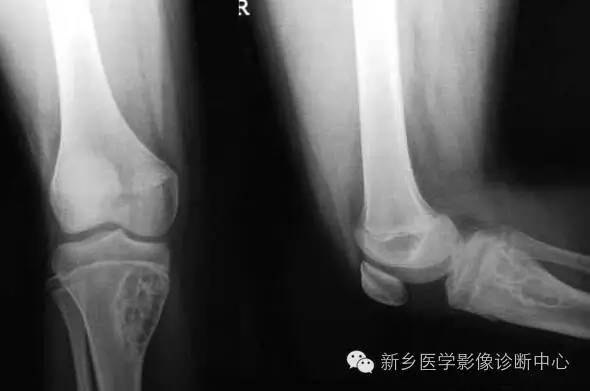

长骨中好发股骨、胫骨的干骺端;多见于30 岁以下;多为隐痛,服水杨酸类药物不能缓解。病理由血供丰富的结缔组织基质及其中大量成骨细胞及巨细胞构成。

在长骨为髓腔内沿骨干长轴走向的长椭圆形地图样骨质破坏,内由斑点状、条索状骨化或钙化;边缘清楚,有硬化边;偏心性生长占46%。MRI 骨样组织T1 为低信号、T2 为高信号;病灶内钙化或骨化在各序列均为低信号;周围可见反应性充血水肿;增强骨样组织强化明显,钙化、骨化、囊变、出血区无强化。

读片要点:(皮质型)1、80%为30 岁以下2、好发干骺端,可向骨干、骨端发展3、边缘骨硬化明显4、膨胀较轻5、斑点状、索条状钙化或骨化